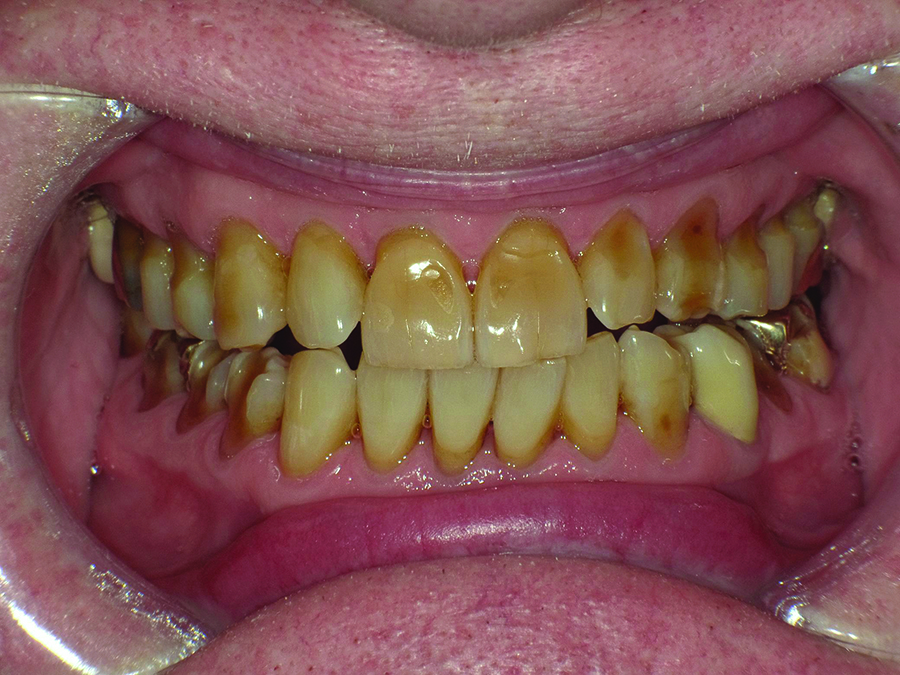

Close-up view of patient’s dentition in 2017 showing increased facial and buccal erosion over the past 8 years.

Figure 2

Biomechanical: Significant tooth structure loss had occurred between 2009 and 2017 (Figure 1 through Figure 3). Severe attrition had occurred on the anterior teeth, especially tooth No. 11. Severe erosion and abrasion were present on teeth Nos. 11, 18, 20, 21, 28, 29, 31, and 32 (Fig-

ure 4). The patient had generalized sensitivity, and tooth No. 18 was painful due to deep erosion, which approached the pulp chamber. Teeth Nos. 7 and 10 had moved out of position and rotated (Figure 5). The progression of erosion over the 8-year period could also be seen radiographically and was especially noticeable on tooth

No. 18 (Figure 6 and Figure 7). The occlusal resins were lost on the mandibular molars, and the erosion and abrasion from the opposing crowns continued to erode the tooth structure.

Extreme changes in an adult dentition can occur rapidly when multiple risk factors are combined. In the case presented, the male patient’s dentition changed dramatically over an 8-year period due in large part to gastroesophageal reflux disease (GERD) and daytime clenching. Significant generalized enamel and dentin loss had occurred, and the patient’s maxillary lateral teeth had shifted despite a healthy periodontium.